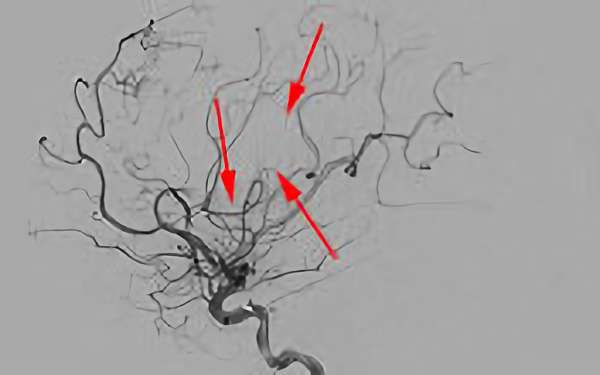

No.623 手術前

No.623 手術中

No.623 手術後